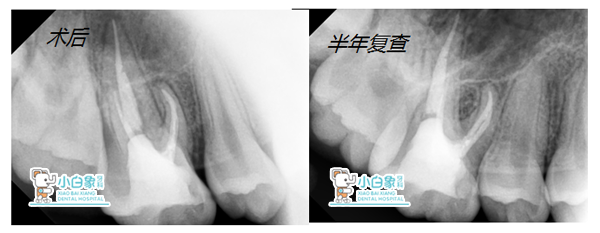

治疗过程:16必兰麻下去腐质揭髓顶大量渗出,丁香油棉捻安抚后封慢失一周。复诊16叩(土),去暂封,拔髓,腭侧及远中颊侧根长19mm,近中颊侧及MB2长18mm,M3预备,常规冲洗,隔湿干燥,热牙胶充填,Z350充填。

医嘱:注意口腔卫生,早期修复。